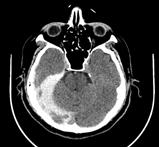

Por otro lado, se quiere señalar la importancia de la ecografía a pie de cama en la Atención Primaria. Tras el empeoramiento clínico del paciente, se pudo valorar de una forma fácil y accesible (a través de la imagen ecográfica) una hepatomegalia que no se palpa o una posible esplenomegalia, ya que constituyen dos de las complicaciones más graves de esta entidad. En concreto, la rotura esplénica que, aunque es infrecuente (en torno 1-2 casos por cada 1000), es potencialmente grave fundando una de las principales causas de muerte en relación a la mononucleosis infecciosa. En consecuencia, la ecografía nos acompañará en el seguimiento para poder medir los cambios a través de un manejo integral desde el centro de salud (7) (Figura 1).

Figura 1.

Imagen ecográfica de bazo de tamaño y morfologías normales. Frecuencia de manifestaciones clínicas de mononucleosis infecciosa (flecha azul, frecuencia de edema periorbitario).